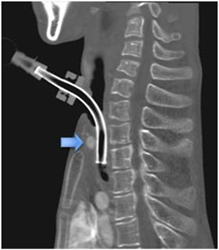

3)分泌物増加に注意(気管カニューレ装着者)

4)気管カニューレに注意(腕頭動脈瘻からの出血)

(2)器官カニューレへの注意事項

@気管内肉芽の形成

カニューレによる慢性刺激によって、気管内肉芽が出来やすくなります。

A腕頭動脈唐の出血

気管内カニューレが湾頭動脈を慢性的に刺激し、それを損傷させる事があります。

その場合、腕頭動脈らの大出血が起こります。

8例/172例---生存=4例、死亡=4例